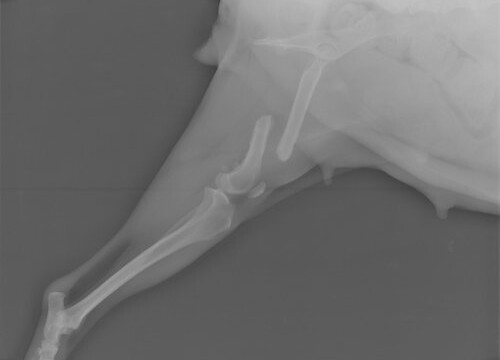

Tilly wurde am 19.2.2013 kastriert und da haben wir nochmal ein Kontrollröntgen machen lassen. Auf diesem Foto kann man sehr gut erkennen, dass der Knochen kürzer ist.

Am 30.9.2013 hat Tilly die Platte an ihrem Oberschenkel wieder rausbekommen. Es geht ihr gut und sie hüpft schon wieder rum. Die OP hat 130 Euro gekostet.